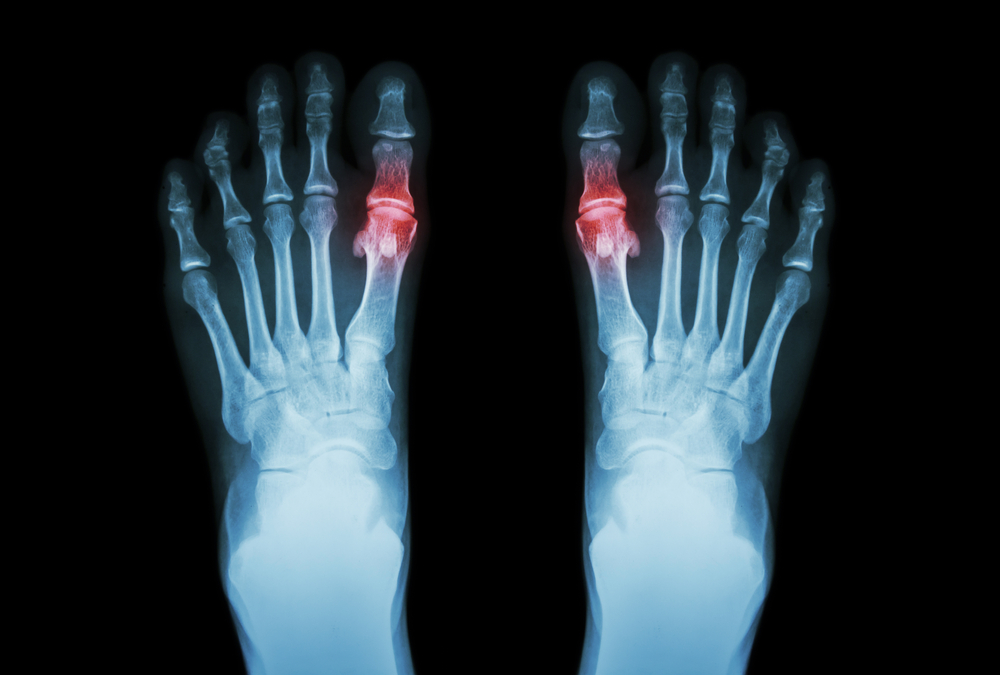

8 Things You Can Do About Foot Arthritis

As we grow older, suffering from arthritis in the foot is one of the most common pains that many people face at some point in their life. Joints and tendons throughout your body begin to show signs of wear and tear from their use and exertion over the years, leading...